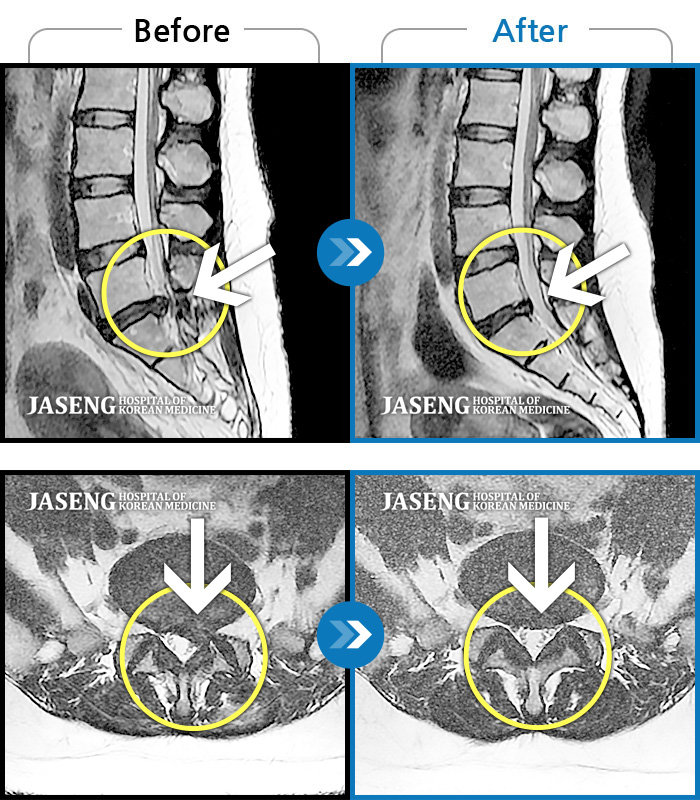

허리디스크

일산 · 김태용 원장

허리 골반통증이 극심했다.

촬영시기

2021.02.06 ~ 0222.01.15

2022.01.17